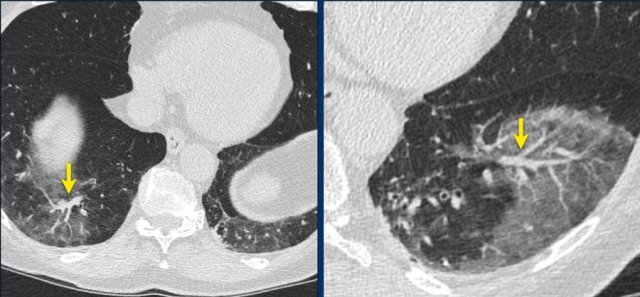

Images of a 59 year old male who had fever for one week with non-productive cough.

The PCR-test was negative.

Because of clinical suspicion a CT was performed which showed some areas of GGO and massive consolidation in the posterior parts of the lower lobes (arrow on sagittal reconstruction).

Two days later a sputum test was positive for COVID-19.